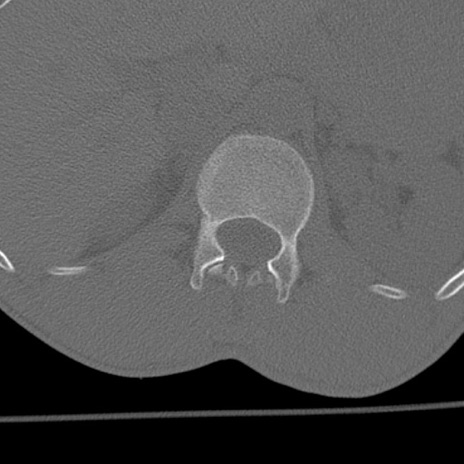

症例3 腰椎CT(横断像)

腰椎CT